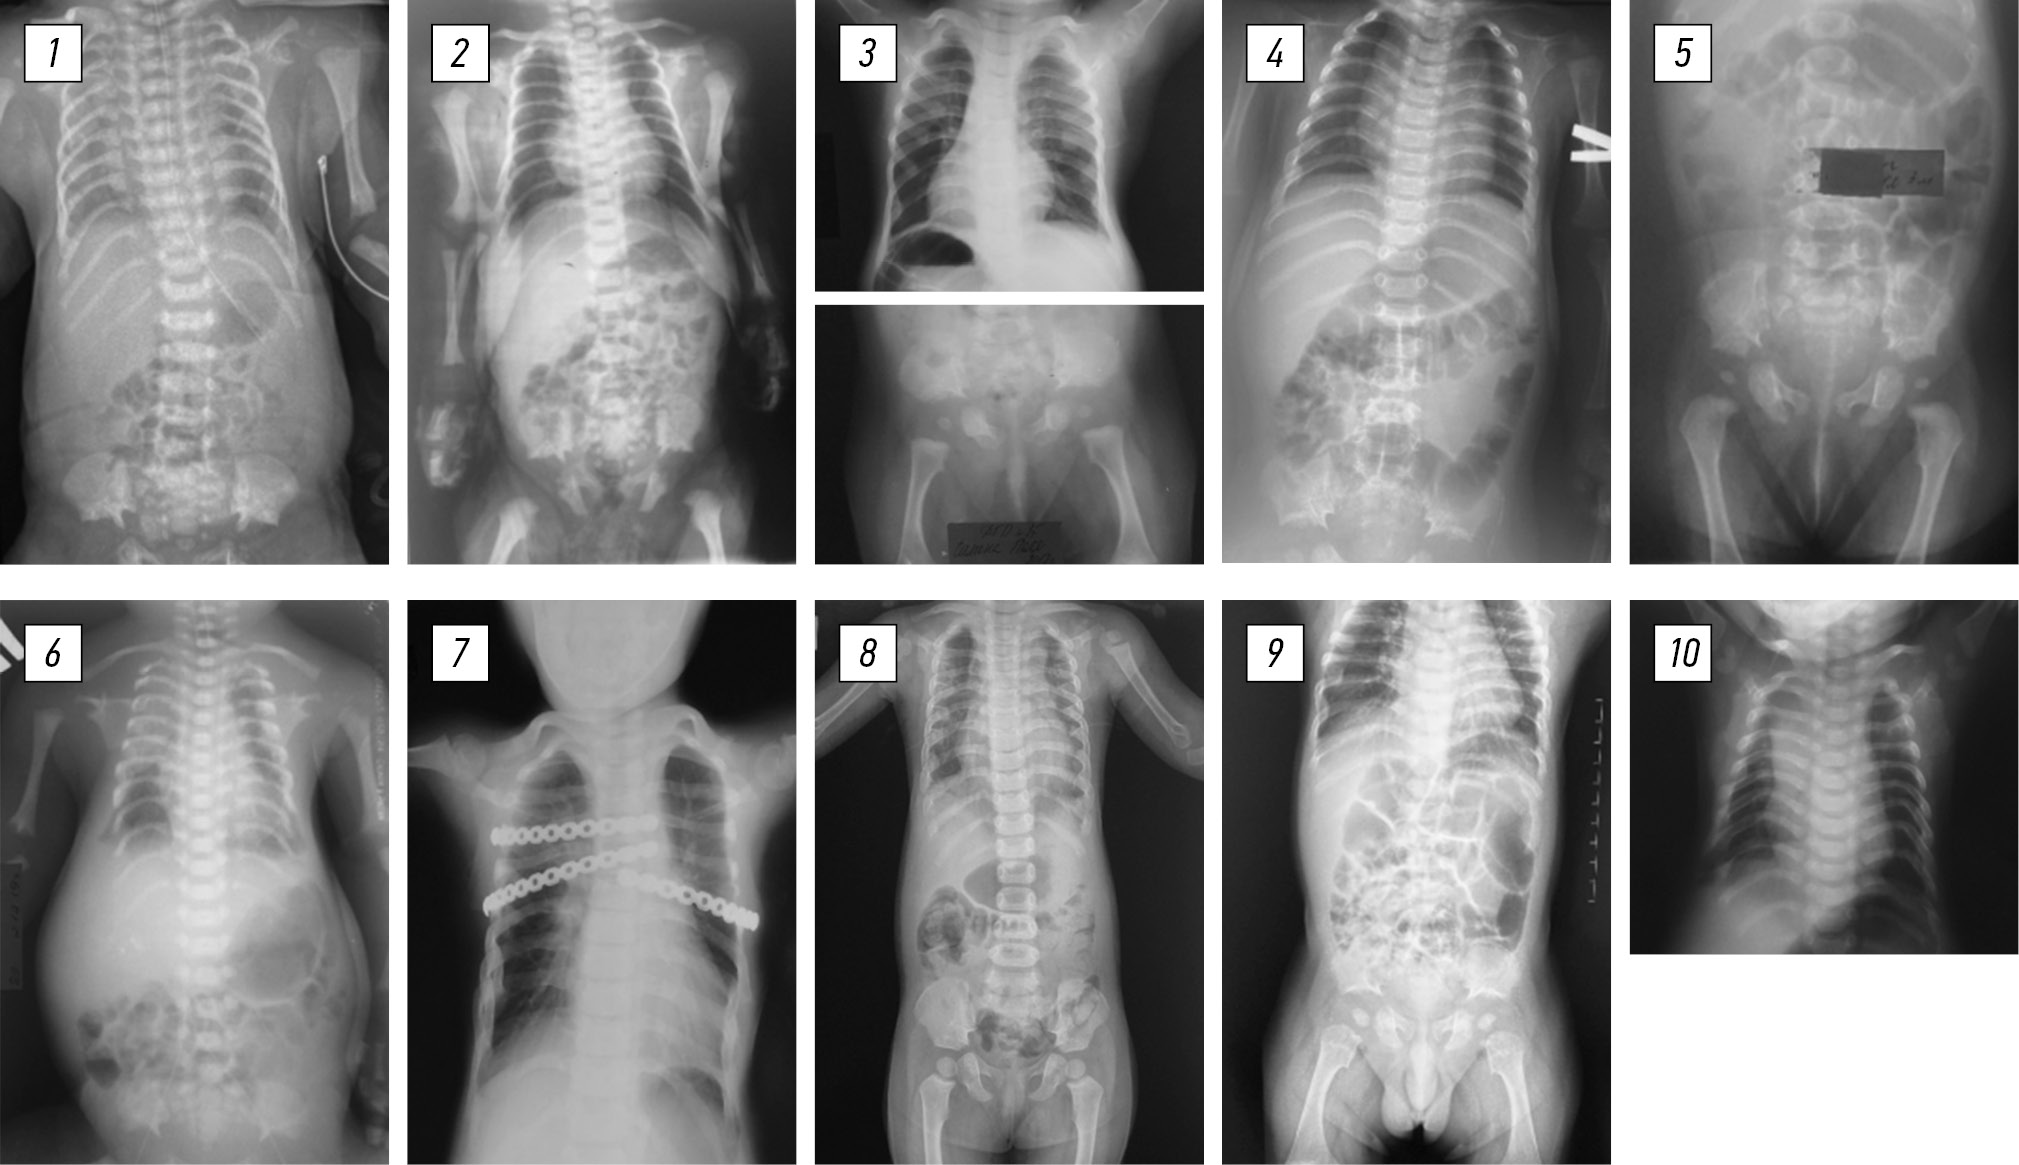

У всех пробандов общими клиническими проявлениями были сужение и деформация грудной клетки разной степени выраженности (рис. 1). Синдром дыхательных расстройств в неонатальном периоде развился у трех из десяти пробандов (30 %), в связи с чем проведена продолжительная дыхательная поддержка СРАР пробанду 3 и осуществлен перевод на искусственную вентиляцию легких пробандов 6 и 9. Несмотря на это, у пробанда 6 на фоне гипоплазии легких и тяжелых кардиореспираторных нарушений на 16-е сутки жизни наступил летальный исход.

Рис. 1. Внешний вид десяти пациентов с торакальной дисплазией

У всех пробандов зарегистрированы уменьшение в поперечном размере грудной клетки, укорочение и горизонтальное расположение ребер, грудная клетка была цилиндрической или колоколообразной формы, а у ряда больных отмечалось утолщение передних отделов ребер (рис. 3). У пробанда 3 диагностирован врожденный двусторонний вывих бедра, по поводу которого проводили консервативное лечение с положительным эффектом.

Рис. 3. Рентгенограммы грудной клетки и тазобедренных суставов десяти пациентов с торакальной дисплазией